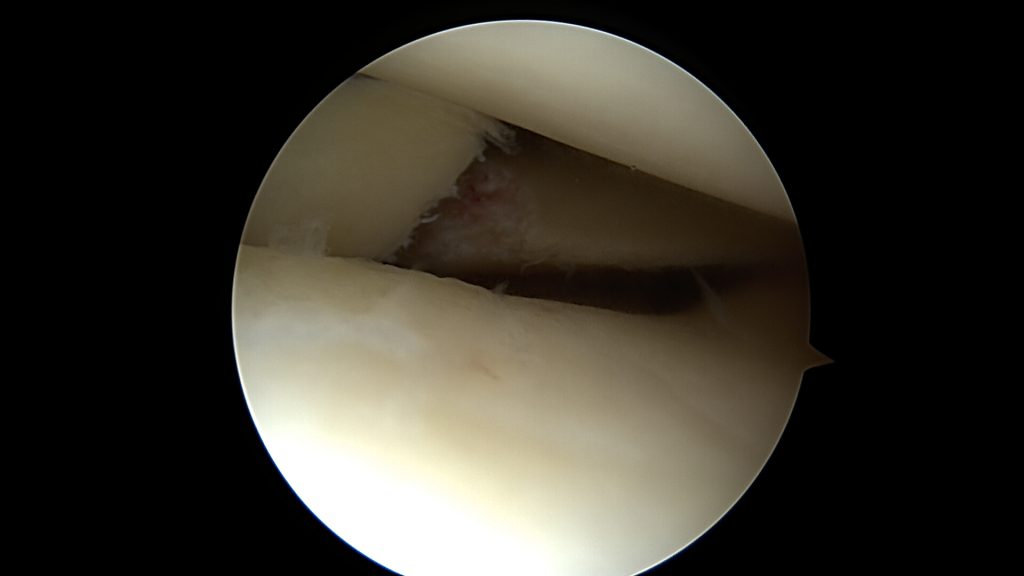

Potwierdzenie rozpoznania tego uszkodzenia następuje podczas zabiegu bardzo szybko. Zaraz po wprowadzeniu optyki do stawu po prostu widzimy łąkotkę nie tam gdzie powinna być, czyli tuż przed kamerą. Po wykonaniu inspekcji wszystkich dostępnych części stawu dokonuje się odświeżenia miejsca uszkodzenia oraz „repozycji” uszkodzonego fragmentu łąkotki (przepchnięcia jej na swoje miejsce). Następnie przy pomocy szwów zakładanych artroskopowo mocują się ją na swoim miejscu.

Jeśli jednak w trakcie urazu ulegnie ona większemu uszkodzeniu, rozkawałkowaniu, lub gdy będziemy zwlekać z zabiegiem operacyjnym, to po wprowadzeniu optyki do stawu naszym oczom ukaże się łąkotka rozwłókniona, popękana, w kilku kawałkach.